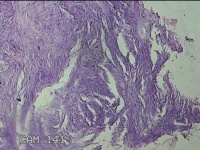

右拇指远端结节

性别

男

年龄

37岁

临床诊断

皮脂腺囊肿

一般病史

发现右拇指远端结节2年余。

标本名称

大体所见

灰白粉红色组织1.8x1.2x00.8cm一个,表面带梭形皮肤1.3x0.7cm,皮下见结节1.2x0.8cm一个,切开结节呈实性,切面灰白粉红色,质中。

图3